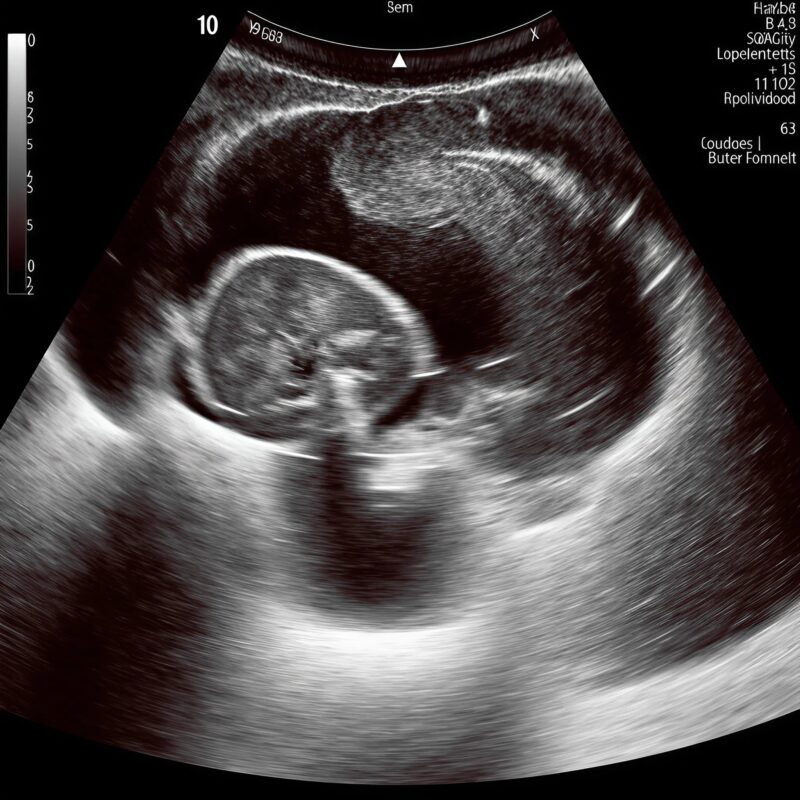

We saw our baby before we heard our baby. The room was dim, cool, all quiet whirs and soft beeps. On the screen, the spine appeared first—white pearls threaded in a graceful arc—until the pearls slipped apart. A small darkness opened where brightness should have been, a pause in the music of bone. I felt the air leave my chest like a door pulled shut. David’s hand found mine;

his fingers were cold and shaking, the way mine would be if I let go. The sonographer slowed her movements, measuring, capturing, circling with a dotted line that looked too much like a target. I stared at that gap and thought the most foolish thing: if I could touch it, maybe it would close. 🤲

The doctor came in with calm shoulders and a steady voice. “We see a discontinuity,” he said, “perhaps a lesion along the lower spine. Sometimes it’s treatable. We’ll take this step by step.” His mouth kept moving, but all I could hear was the watery thud of our baby’s heart.

At home, we didn’t plan a nursery theme or fold tiny onesies into neat stacks. We learned new words. Neural tube. Sacral. Closure. We pinballed between hope and fear and strange, clinical brightness. I slept on my side, one hand on my belly, whispering to the small swimmer inside: I’m here. I won’t blink. I won’t miss a beat. David read studies aloud until the words became river sounds. The world narrowed to appointments, measurements, the architecture of weeks.The second scan was on a different machine, larger, its interface resembling a cockpit. The spine appeared again, white beads along a riverbank. The gap was still there—only now it seemed to shift, like a door trying to decide whether to be open or closed. The doctor adjusted angles, increased depth, changed probes.

“There’s an acoustic shadow interfering,” he murmured. “But we can’t assume artifact. We prepare for both.” He drew diagrams: delivery in a specialized unit, neonatal surgery if needed, the choreography of teams and minutes. I nodded, memorizing each step like a dance whose music I didn’t yet know. 💙

Week twenty-two. The images grew sharper; the baby grew angles. The placental lake looked like a halo. The spine brightened like a road at dawn. And always, the pause—a short break in the line. The surgeon met us in a room with a frosted window, hands warm, eyes straightforward. “If there’s an open lesion, we’ll protect the area at birth and plan early repair,” she said. “We’re better at this every year.” She smiled, not the smile that says don’t worry, but the one that says I’ll be there when you do. I carried that smile home like a lantern. 🕯️

In the last scan—one more machine, one more monitor—the gap looked different. The sonographer frowning, then adjusting, then frowning again. “I need to try one thing,” she murmured. She repositioned our son on his side, lifted his tiny leg with astonishing gentleness, and angled the probe along a narrow corridor of sound. The image sharpened. The beads of the spine lined up, one after the other, unbroken. Where the darkness had opened before, light threaded through like a needle. The room stayed silent long enough for me to believe it, and then the sonographer laughed, a soft breath of disbelief.

“It’s not a lesion,” she said. “It’s an artifact. An acoustic shadow.”

The neonatologist exhaled with his whole body. The surgeon leaned in to confirm, tracing the white line with a gloved finger on the screen. “The shadow was cast by something maternal,” she said carefully, “likely the hardware from your scoliosis surgery years ago. The angles we used during pregnancy kept catching it right here.” She tapped the place where fear had lived for months. Relief did not arrive like a trumpet. It arrived like tidewater, slow and certain, pulling broken shells back to sea. I began to laugh and cry at once. David bent over our son’s blanket and whispered, “You trickster. You little comet.” 🌈